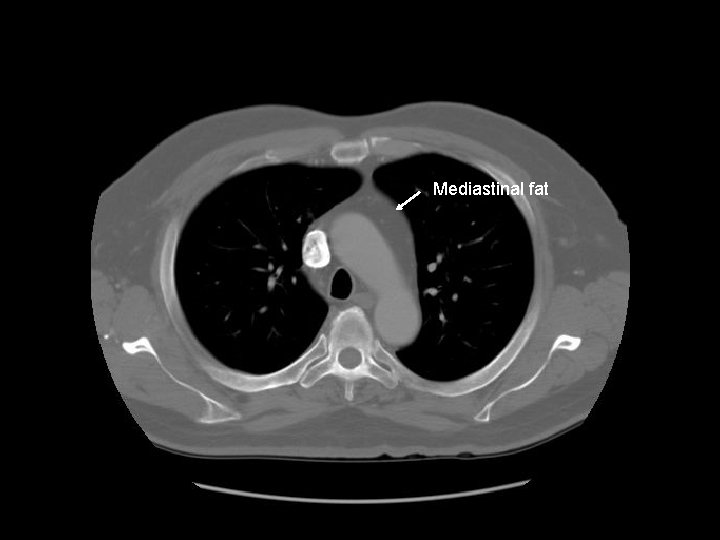

Mediastinal fat